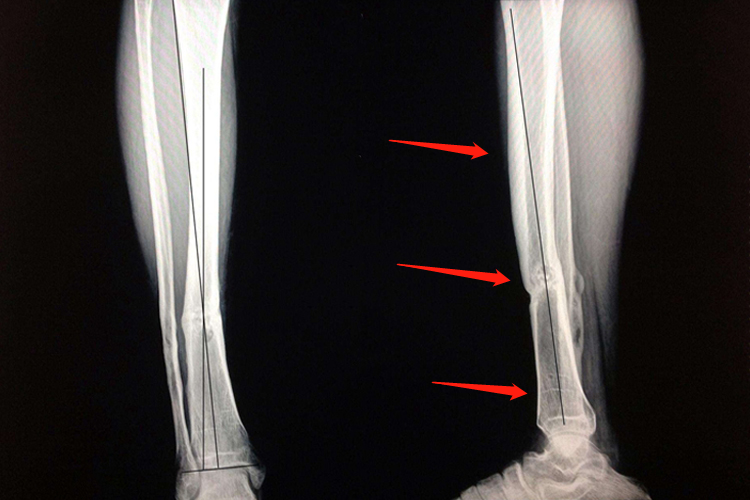

胫骨骨折畸形愈合:是指骨折断端在重叠、旋转、成角状态下连接,而引起肢体功能障碍。X线上显示胫骨骨折端产生的骨痂较少、骨折线不消失、骨折断端无硬化现象,且有轻度脱钙。

胫骨骨折迟缓愈合:胫骨骨折经治疗后,已超过同类骨折正常愈合的最长期限,骨折处局部仍有肿胀、压痛,纵轴叩击痛,异常活动,功能障碍。X线片显示骨痂生长缓慢而未连接,但骨折断端无硬化现象,骨髓腔仍通。

胫骨骨折不愈合:是指胫骨骨折愈合功能停止,骨折端已形成假关节。X线片显示胫骨骨折端互相分离,间隙增大,骨端硬化或萎缩疏松、髓腔封闭,用一般的固定方法无法使之连接。